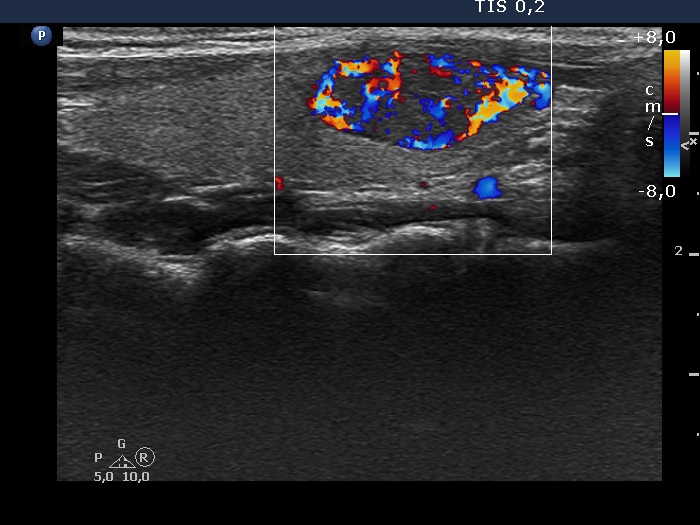

Second examination 3 years later (second row of images)

Clinical data: The patient had no complaints.

Palpation: unchanged.

Laboratory test: TSH 0.79 mIU/L.

Ultrasonography. Both the pattern and the size of the nodule in the right lobe remained unchanged. The cystic content of the left lobule has disappeared, it was replaced by inhomogeneous solid part. The vascularization of this lesion has also changed, the intranodular vascularization has become significantly increased.

Suggestion ultrasound in three years.